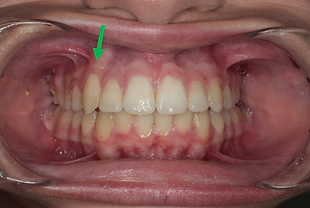

בסיום הטיפול האורתודונטי שתי השיניים נמצאות בפה

בסיום טיפול

בסיום הטיפול האורתודונטי השן הכלואה בפה